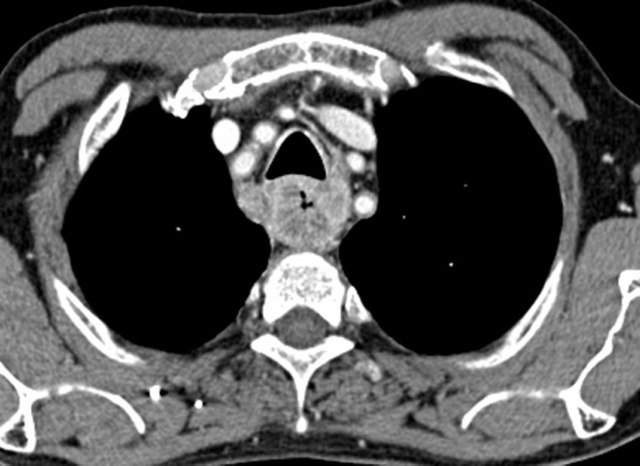

Esophageal cancer is in the top 10 common cancers around the world. For an advanced stage of this cancer, at stages II-III, the standard treatment is to go through chemotherapy (to chemically destroy cancer cellsโ ability to replicate) and radiotherapy (to break cancer DNA with high-energy light), before the esophagectomy to resect the tumor. This order allows minimal cancer seeding with surgical removal, as undetectable number of cancer cells may remain even when the visible mass is removed. There is a recent study that suggests chemoradiotherapy alone may yield the same rate of mortality as chemoradiotherapy and surgery combined. This paper seeks to compare definitive chemoradiotherapy vs. neoadjuvant chemoradiotherapy plus surgery of esophageal and gastroesophageal cancer through means of systematic review and meta-analysis. Relevant records from Medline, Embase, and Cochrane Central Register of Controlled Trials, as well as literature from American Society of Clinical Oncology and European Society of Medical Oncology were sought. The articles with randomized controlled trials or observational studies with survival and/or toxicity data were chosen. A total of 8 articles, with 16,647 patients, were included for analysis. Overall, the neoadjuvant chemoradiotherapy with esophagectomy showed higher rates of survival compared to those who received definitive chemoradiotherapy. Regarding side effects, the combination therapy with surgery resulted in higher rates of anastomotic leak, esophageal necrosis, recurrent nerve paralysis resulting in hoarse voice, and pulmonary complications. The definitive chemoradiotherapy saw more rates of anemia, leukopenia, and nausea/vomiting.